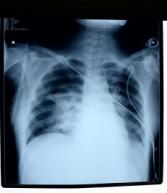

入院时的胸部X线片:见图1

图1